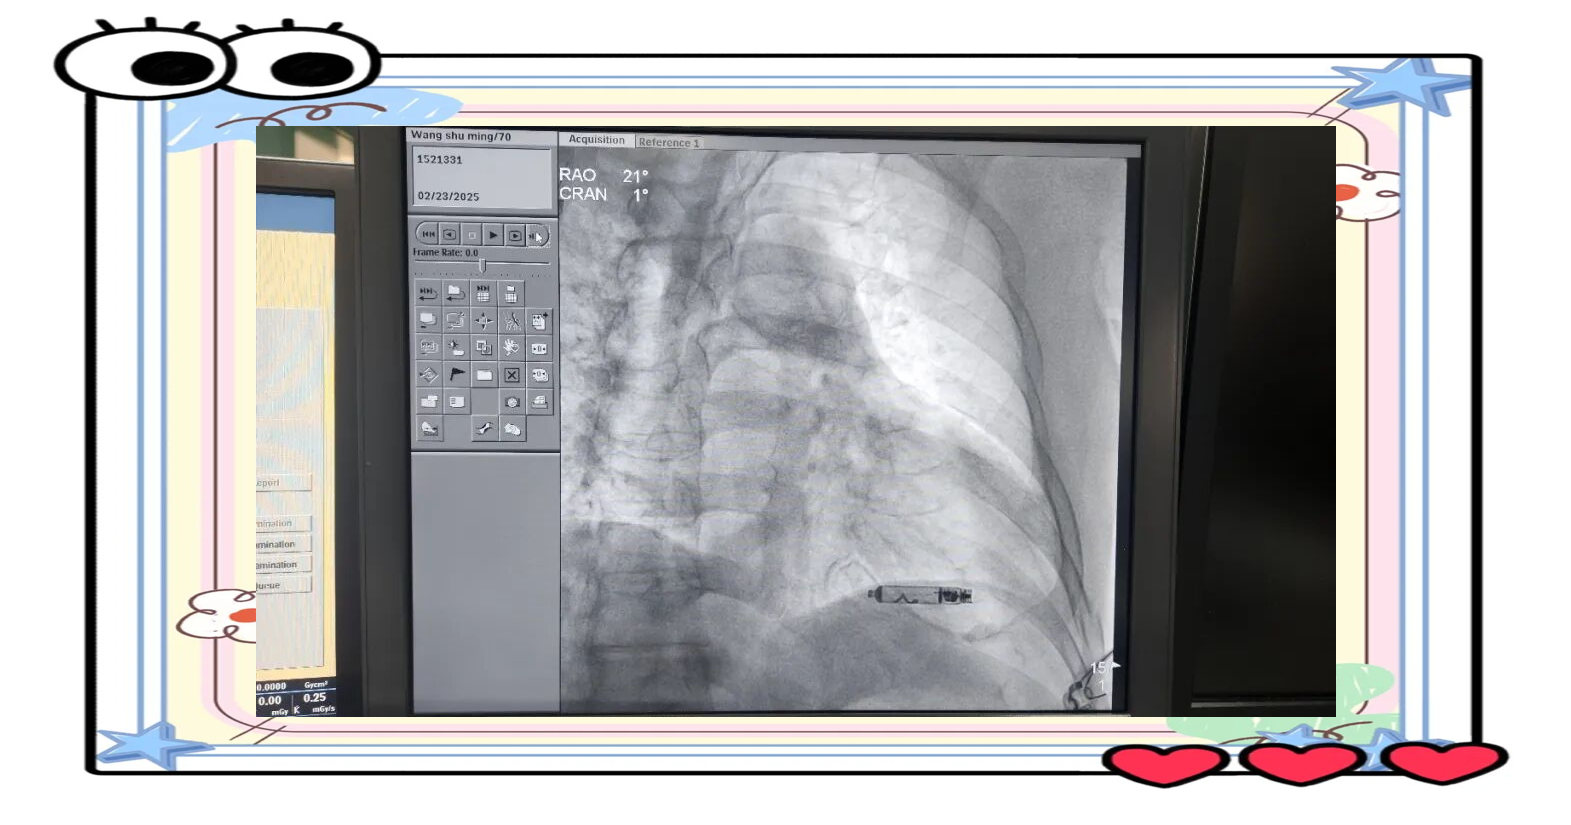

值得关注的是,这款起搏器体积非常小巧,形状近似胶囊,对人体组织友好,不易引发排异或凝血,可以通过微创导管经股静脉植入心脏内部,大大降低手术创伤。科研团队独创了一套极简的磁悬浮储能结构,这项设计不仅减少了能量损耗和内部摩擦,还实现了近零启动阈值、高效能量转换和持续稳定的功率输出,在简化整体结构的同时,也显著提升了设备长期工作的可靠性。